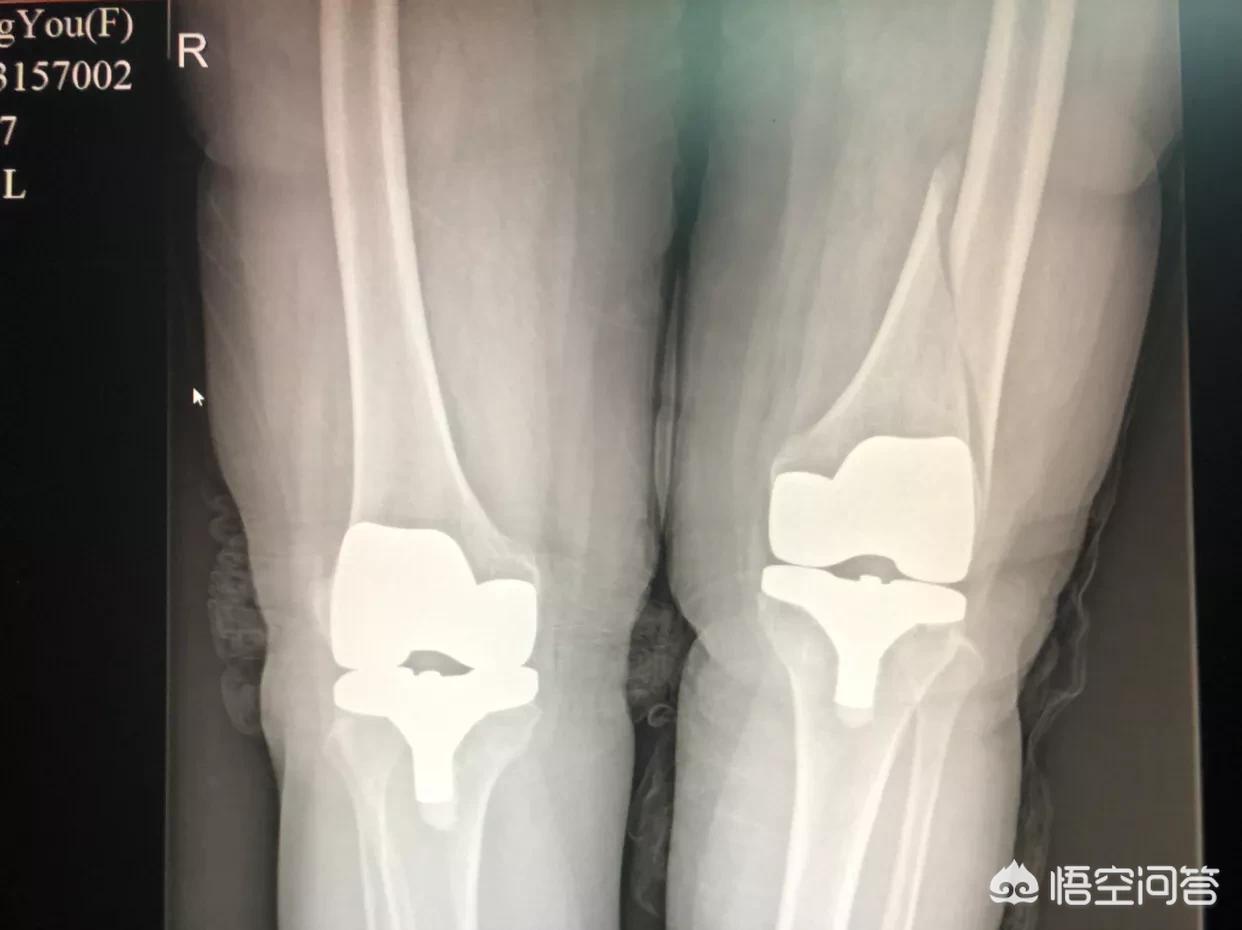

钢板内固定

前面两种都可以全是保守治疗,是不用开刀的,而钢板内固定是要开刀的!

简单说手术过程就是:在骨折部位开刀切进去,暴露骨折断端,在直视下复位骨折,然后装上钢板,拧上螺钉固定。

优点:1、术中基本可以达到解剖复位,基本不会畸形愈合,除非是有些粉碎性骨折,骨折碎片太多了,没办法拼起来;

2、坚强的内固定或者说比较牢固的内固定,术后几天就可以下地走路,基本生活自理,大大减少了上述所说的长期卧床来的并发症,早期就可以行功能锻炼;

3、钢板在人体体内,不影响生活,大大提高了生活质量(你想下石膏固定睡觉时候也要带着,自己体会!);

缺点:1、年轻人的内固定还是建议骨折愈合后取出的,因此可能要做第二次手术取出内固定;

2、破坏了骨折处血肿的营养基,对于一些老年人不利于骨折恢复,但总体上还是比不做手术强;

3、钢板内固定价格昂贵!